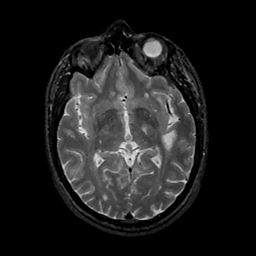

MR Study #11, May 5, 1991 -- Slice #24